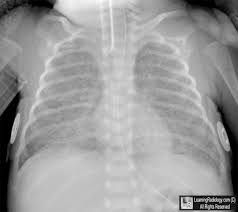

Learningradiology Bronchopulmonary Dysplasia Bpd Chronic Lung Disease Infancy Immature Radiology

Pediatric Imaging Na Twitteru Chronic Lung Disease Etiology Premature Infants With Rds Who Are Chronically Ventilated For Than 30 Days Imaging Normally Expanded Lungs With Interstitial Scaring Cxr Findings